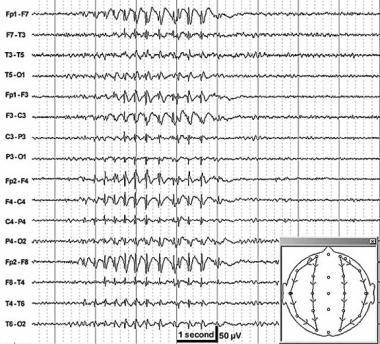

What is an absence seizure, what would the EEG show + what are the triggers?

Brief staring spell, usually in children

EEG shows 3 second spike-wave pattern

Triggers = hyperventilation + flashing lights